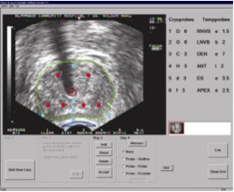

Treatment planning software is used to precisely design the size and shape of the iceball